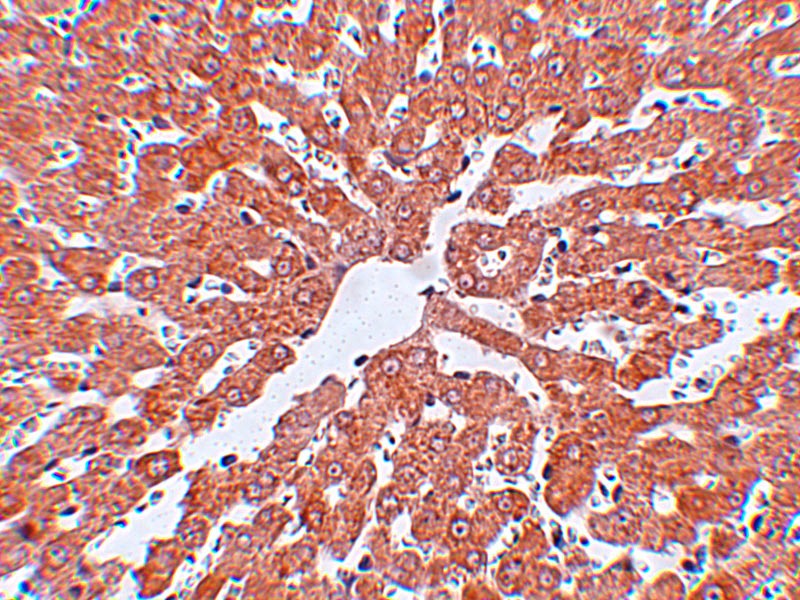

图片:

Immunohistochemistry of IRAK in rat liver tissue with IRAK antibody at 2.5 ug/mL.